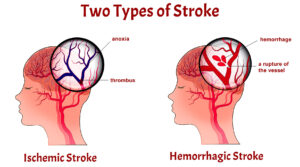

انواع سکته مغزی

سکته های مغزی به سه دسته اصلی تقسیم میشوند:

حمله ایسکمیک گذرا (TIA) ، سکته مغزی ایسکمیک و سکته مغزی هموراژیک.

سکته مغزی ایسکمیک

در طی سکته ایسکمیک ، شریان های خونرسانی به مغز باریک می شوند یا مسدود می شوند.

این انسداد در اثر لخته شدن خون یا جریان خون ایجاد می شود که به شدت کاهش می یابد.

همچنین می تواند در اثر تکه های پلاک در اثر تجزیه تصلب شرایین و انسداد رگ خونی ایجاد شود.

دو نوع متداول در سکته های ایسکمیک ، ترومبوتیک و آمبولی است.

سکته مغزی ترومبوتیک زمانی اتفاق می افتد که در یکی از شریان های خونرسانی به مغز لخته خون ایجاد شود.

لخته از جریان خون عبور کرده و در رگ ها رسوب میکند ، که مانع جریان خون می شود.

سکته مغزی آمبولیک زمانی است که لخته خون یا بقایای دیگری در قسمت دیگری از بدن تشکیل شده و سپس به مغز می رود.

سکته هموراژیک

سکته هموراژیک زمانی اتفاق می افتد که یک سرخرگ در مغز پاره شود و خون ریزی کند.

خون حاصل از آن شریان فشار اضافی در جمجمه ایجاد کرده و مغز را متورم می کند و به سلول ها و بافت های مغز آسیب می رساند.

دو نوع سکته مغزی خونریزی دهنده داخل مغز و زیر عنکبوتیه است، متداول ترین نوع سکته مغزی خونریزی دهنده ،

هنگامی اتفاق می افتد که بافت های اطراف مغز پس از ترکیدن رگ ، خون پر شوند.

سکته هموراژیک زیر عنکبوتیه کمتر شایع است. باعث خونریزی در ناحیه بین مغز و بافتهایی می شود که آن را پوشانده اند.